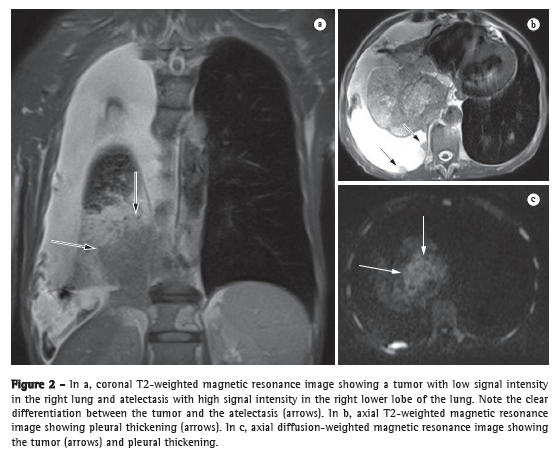

Diagnosis

If a patient suspected of having PH has been screened and signs consistent with increased pressure levels in the pulmonary circulation have been detected in the initial tests, the need to perform RHC to confirm the diagnosis of PH should be evaluated, because a definitive diagnosis of PH can only be established by invasive pressure measurements (Figure 3).

Since the last Brazilian consensus, there have been changes in the definition of PH. Before the meeting in Dana Point, CA, PH was defined as mean PA pressure (MPAP) ≥ 25 mmHg at rest or ≥ 30 mmHg during exercise, with pulmonary capillary pressure ≤ 15 mmHg. The group of specialists who reviewed the data that had been published up until the time of the meeting concluded that the data collected during exercise were extremely heterogeneous regarding the load used, the duration of the exercise, and the position of the patient during exercise, factors that might influence PA pressure measurements. Due to this lack of standardization, a decision was made to remove exercise-induced PH from the definition of PH. This does not mean that exercise-induced PH does not exist; it only means that the data collected to date are not sufficiently robust to provide a definition of exercise-induced PH values. This underscores the importance of conducting new studies in this field in order to provide an appropriate definition of exercise-induced PH.(2)

Patients with MPAP ≥ 25 mmHg are diagnosed with PH, and, after the diagnosis has been established, it must be determined whether the PH is precapillary or postcapillary. If the PA occlusion pressure (PAOP) is ≤ 15 mmHg, the PH is classified as precapillary. If the PAOP is > 15 mmHg, the transpulmonary gradient (TPG) must be determined. The TPG is calculated be the difference between the MPAP and the PAOP. When this difference is ≤ 12 mmHg, the increase in the MPAP is considered passive, which means that the increase in the MPAP is caused exclusively by cardiac involvement. If the TPG is > 12 mmHg, the increase in the MPAP is disproportionate to the increase in left ventricular pressure, indicating that there is pulmonary vascular remodeling or another associated cause of increased MPAP (Chart 1 and Figure 3).